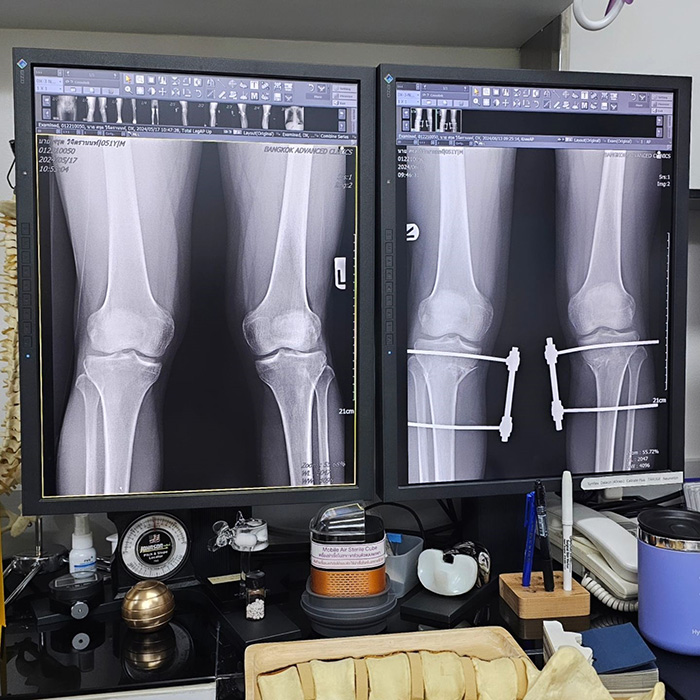

บิ๊ก ศรุต เผยภาพเอกซเรย์เข่า เล่าอาการ Knock knee หรือ ขาฉิ่ง คืออะไร หลังเป็นเหตุทำให้ต้องผ่าตัด ใส่เหล็กที่ขานานเดือนกว่า ทำเอาหลายคนอดเป็นห่วงไม่ได้ หลังจากนักแสดงรุ่นใหญ่ บิ๊ก ศรุต ได้เผยว่ากำลังจะเข้าผ่าตัดแก้ไขปัญหา Knock knee ต้องใส่เหล็กไปยาว ๆ 4-6 สัปดาห์ จนมีคนสงสัยว่าเกิดอะไรขึ้น ป่วยเป็นอะไร แล้วอาการ Knock knee คืออะไร ขณะเดียวกันก็มีแฟน ๆ เข้ามาให้กำลังใจ ขอให้ผ่าตัดเป็นไปอย่างราบรื่น ฟื้นตัวได้เร็ว โดยล่าสุด (13 มิถุนายน 2567) บิ๊ก ศรุต ก็ได้เผยภาพเอกซเรย์เข่าของตนเอง เทียบก่อนผ่า-หลังผ่า พร้อมเล่าถึงอาการ Knock knee หรือ ภาวะขาฉิ่ง ที่ตนเองเป็นอยู่ ว่าคืออะไร ขาเป็นอย่างไรบ้าง ดังนี้ "หลายคนอาจสงสัยว่า Knock knee ที่ผมเป็นคืออะไร ? วันนี้ผมถ่ายฟิล์ม X-Ray ผมมาให้ดูนะครับ วันนี้ผมไป follow up กับคุณหมอมา // ขาข้างขวาวันนี้ทำการปรับองศาใหม่อีก 2° ครับ ตอนนี้ทุกอย่างอยู่ในองศาที่ดีและถูกต้องแล้ว จากนี้ก็ไปพบคุณหมอทุกอาทิตย์จนกว่าจะถอดอุปกรณ์ออกครับ ในฟิล์ม X-Ray ให้สังเกตที่แนวต้นขากับหน้าแข้งของผมก่อนผ่ากับหลังผ่าดูนะครับ ก่อนผ่าเข่าบีบเข้าหากันเยอะอยู่ครับ (ขาฉิ่ง) หลังผ่ารูปร่างของขาโดยรวมเปลี่ยนไปค่อนข้างเยอะเลยทีเดียวครับ บางทีเรามองด้วยตาเปล่าเราแทบไม่รู้สึกนะครับ แต่ในฟิล์มนี่ชัดเลยครับผม หวังว่าโพสต์นี้คงจะมีประโยชน์บ้างกับคนที่เป็นเหมือนผมหรือมีคนรู้จักเป็นนะครับ ขอให้วันนี้เป็นวันที่ดีของทุกคนครับ #knockknee" ทั้งนี้ในเว็บไซต์ คลินิกกายภาพบำบัดก้าวระรินสุข ได้ให้ข้อมูลเกี่ยวกับ ภาวะเข่าชิด (Knock Knee) หรือภาวะเข่าฉิ่ง/เข่าเป็ด หรือ ขาฉิ่ง คือภาวะที่เกิดการบิดหรือหมุนเข้าด้านในของเข่า ทำให้เกิดการชิดกันของเข่า ในขณะเดียวกันขาด้านล่างบริเวณน่องและข้อเท้าวางออกห่างออกจากจุดศูนย์กลางของร่างกาย โดยภาวะนี้สามารถเกิดได้ทั้ง 2 ข้างหรือข้างเดียวก็ได้ โดยภาวะที่เด่นชัดที่สุดหลังเกิดเข่าชิด (Knock Knee) คือ การที่ข้อเท้าแยกออกทางด้านข้างในขณะที่เข่าชิดกัน และอาการอื่น ๆ ที่มักเกิดมาจากลักษณะการเดิน ได้แก่ มีอาการปวดข้อสะโพก ข้อเข่าหรือข้อเท้าขณะเดินหรือทำกิจกรรม มีการติดขัดของข้อต่อ องศาการเคลื่อนไหวของข้อสะโพกหรือข้อเข่าลดลง รูปแบบการเดินผิดปกติ เดินกะเผลก ลงน้ำหนักได้ไม่เต็มที่ ข้อเข่าไม่มั่นคง หากเกิดภาวะเข่าชิด (Knock Knee) เป็นเวลานานอาจทำให้เกิดการเสื่อมของข้อเข่า, เกิดการบาดเจ็บของหมอนรองกระดูกเข่าได้